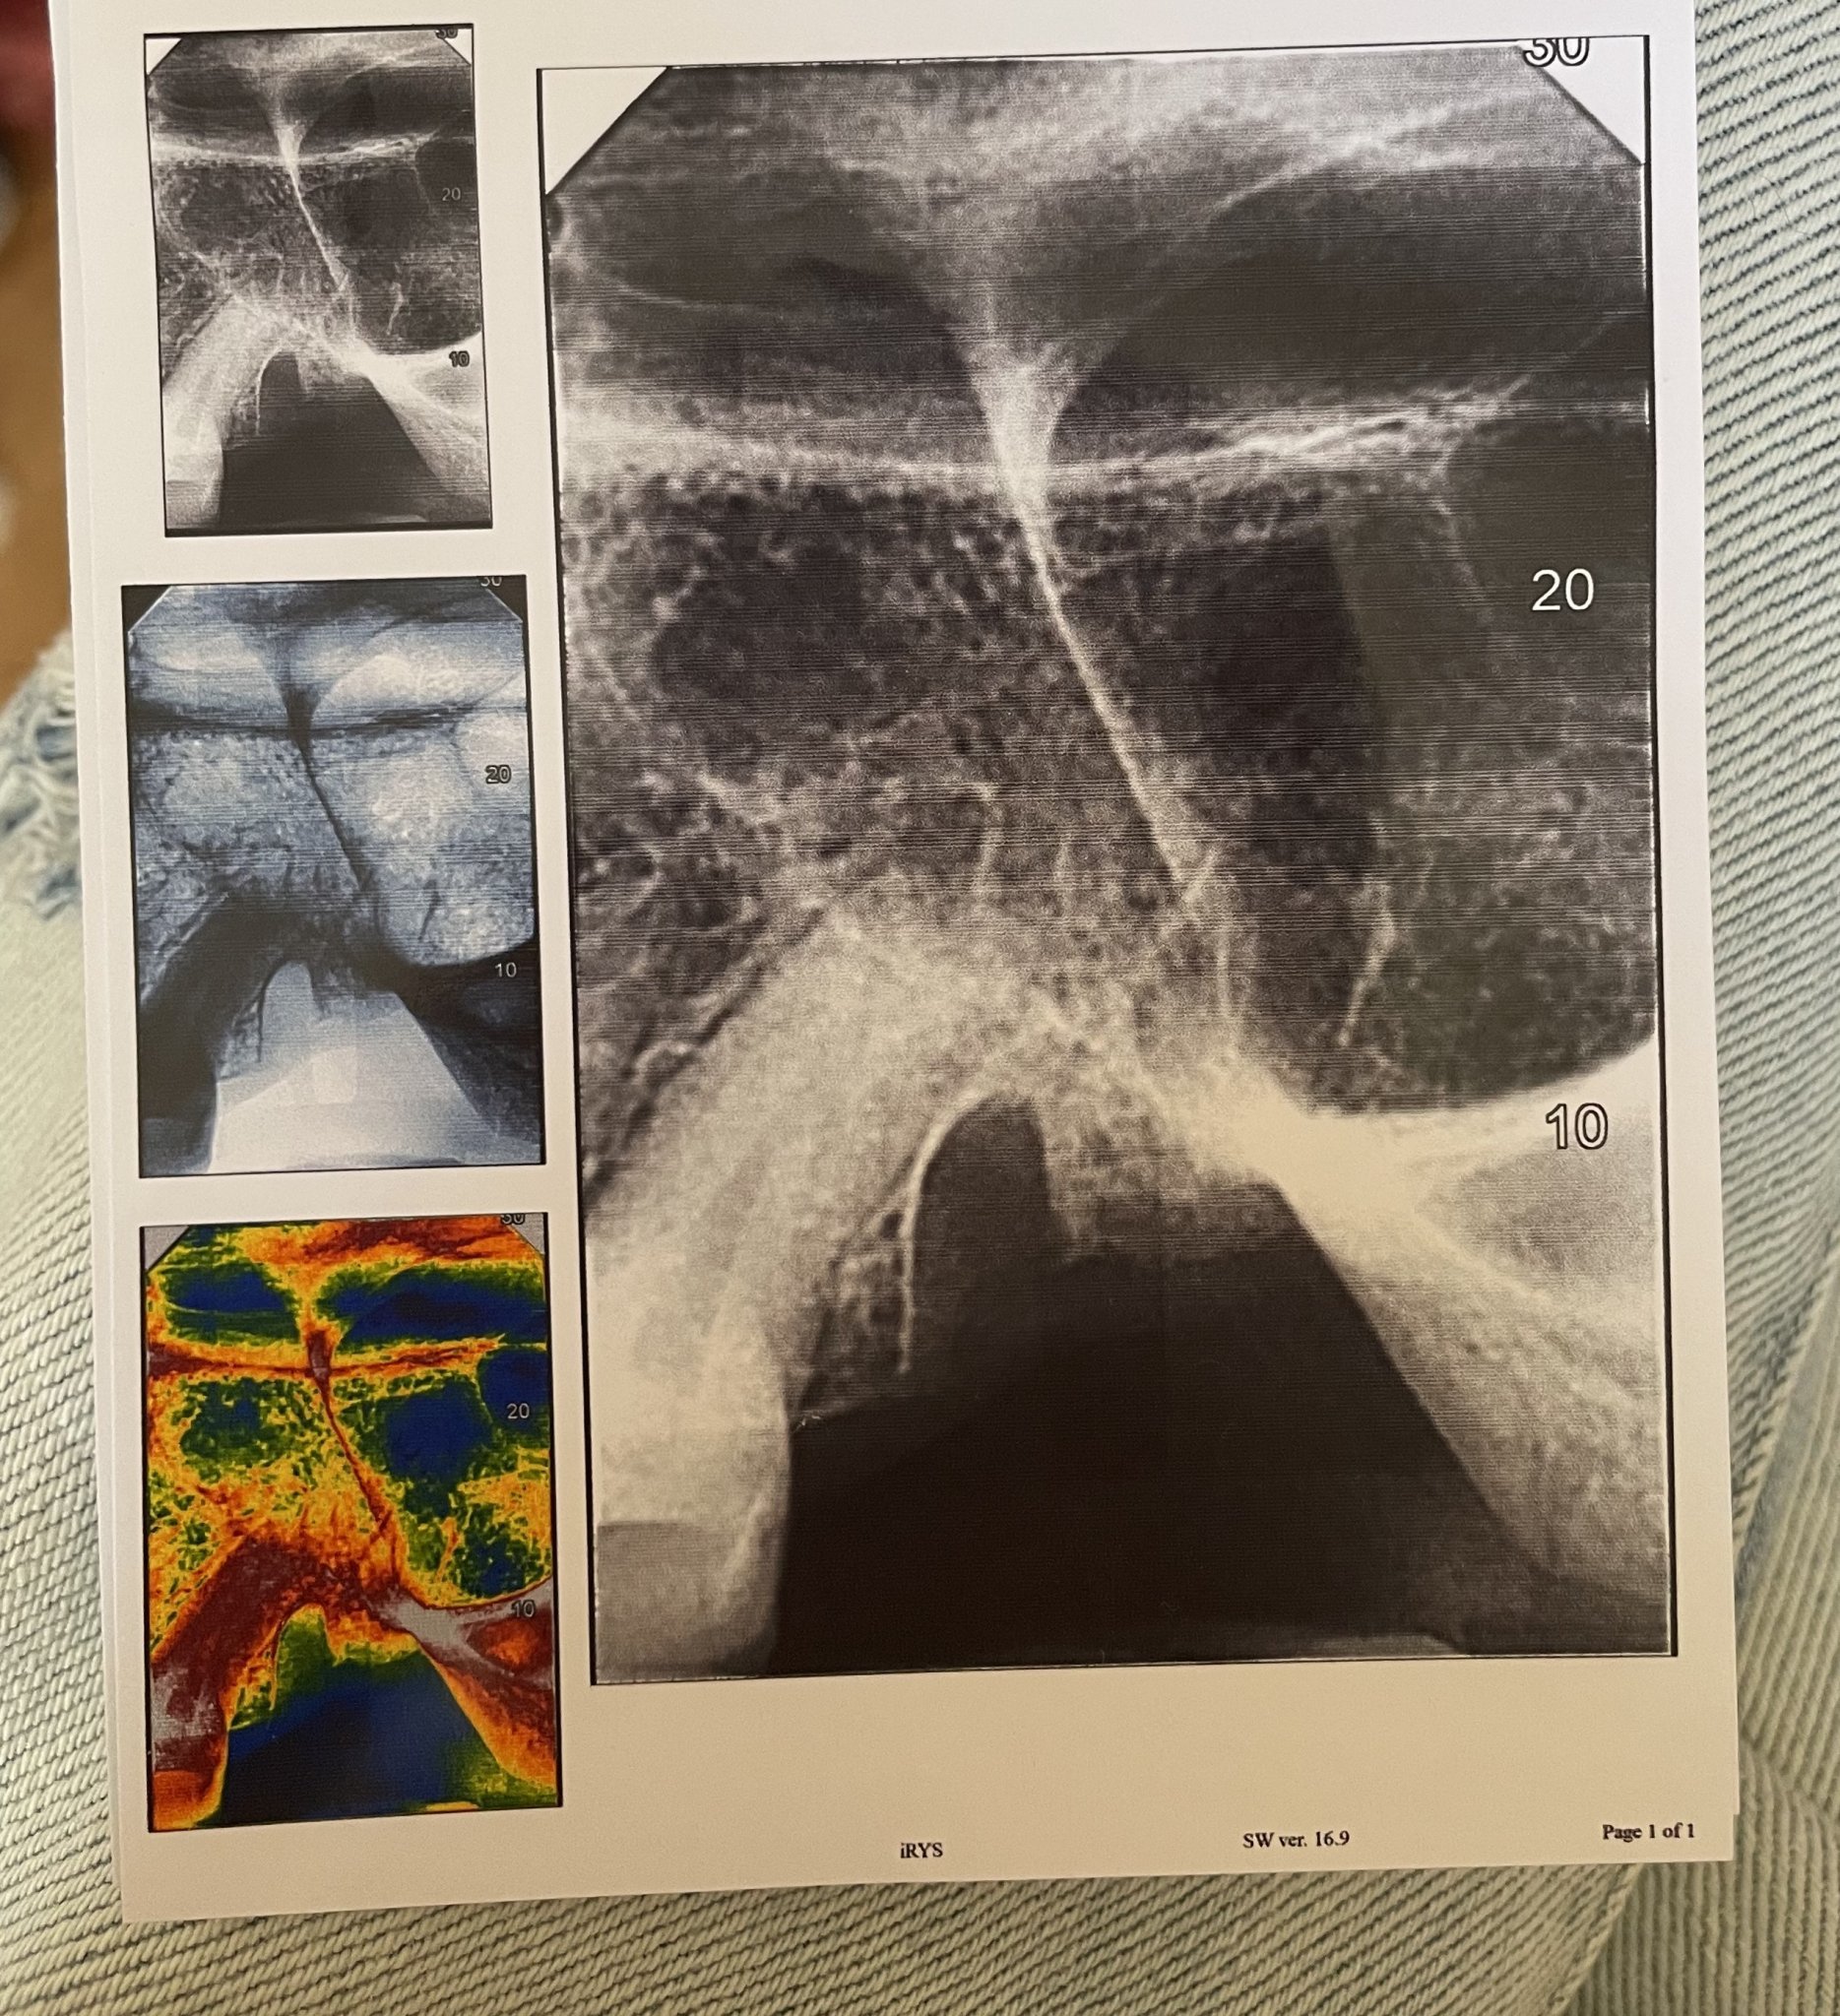

.   Много Ви благодаря за отговора.Днес правих снимка на изваденият зъб и на друг зъб от другата страна ,където също имам болка и чувствам ,че е от зъб.Бихте ли помогнали с разчитането на снимкте?